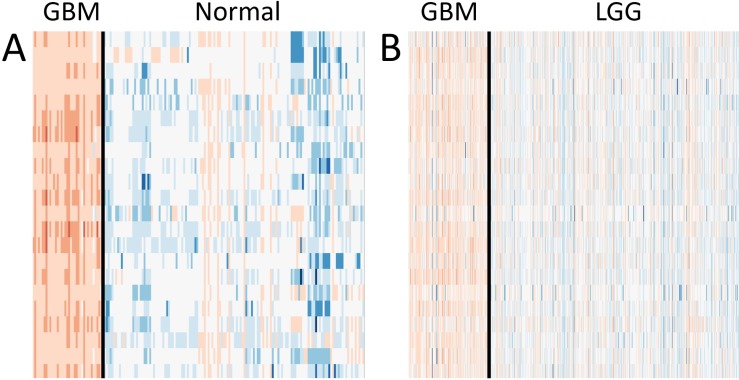

Gene expression analysis reveals GBM-specific upregulation

We investigated the gene expression levels of the 22 genes seen in TCGA M0214 and Brain M0257 in different conditions. Heatmaps and bar graphs were constructed to visualize the expression levels of the 22 matching genes between TCGA M0214 and Brain M0257 (Figures 4A–4B and 5A–5B). All 22 genes showed significantly upregulated expression (Student’s T Test; p < 0.001) in GBM relative to LGG (in the TCGA Network) and relative to normal brain (in the Brain Network). Significance test results are available for the expression of the 22 shared genes in the TCGA GEM (Supplementary Table 6) and in the Brain GEM (Supplementary Table 7).

Internetwork comparisons